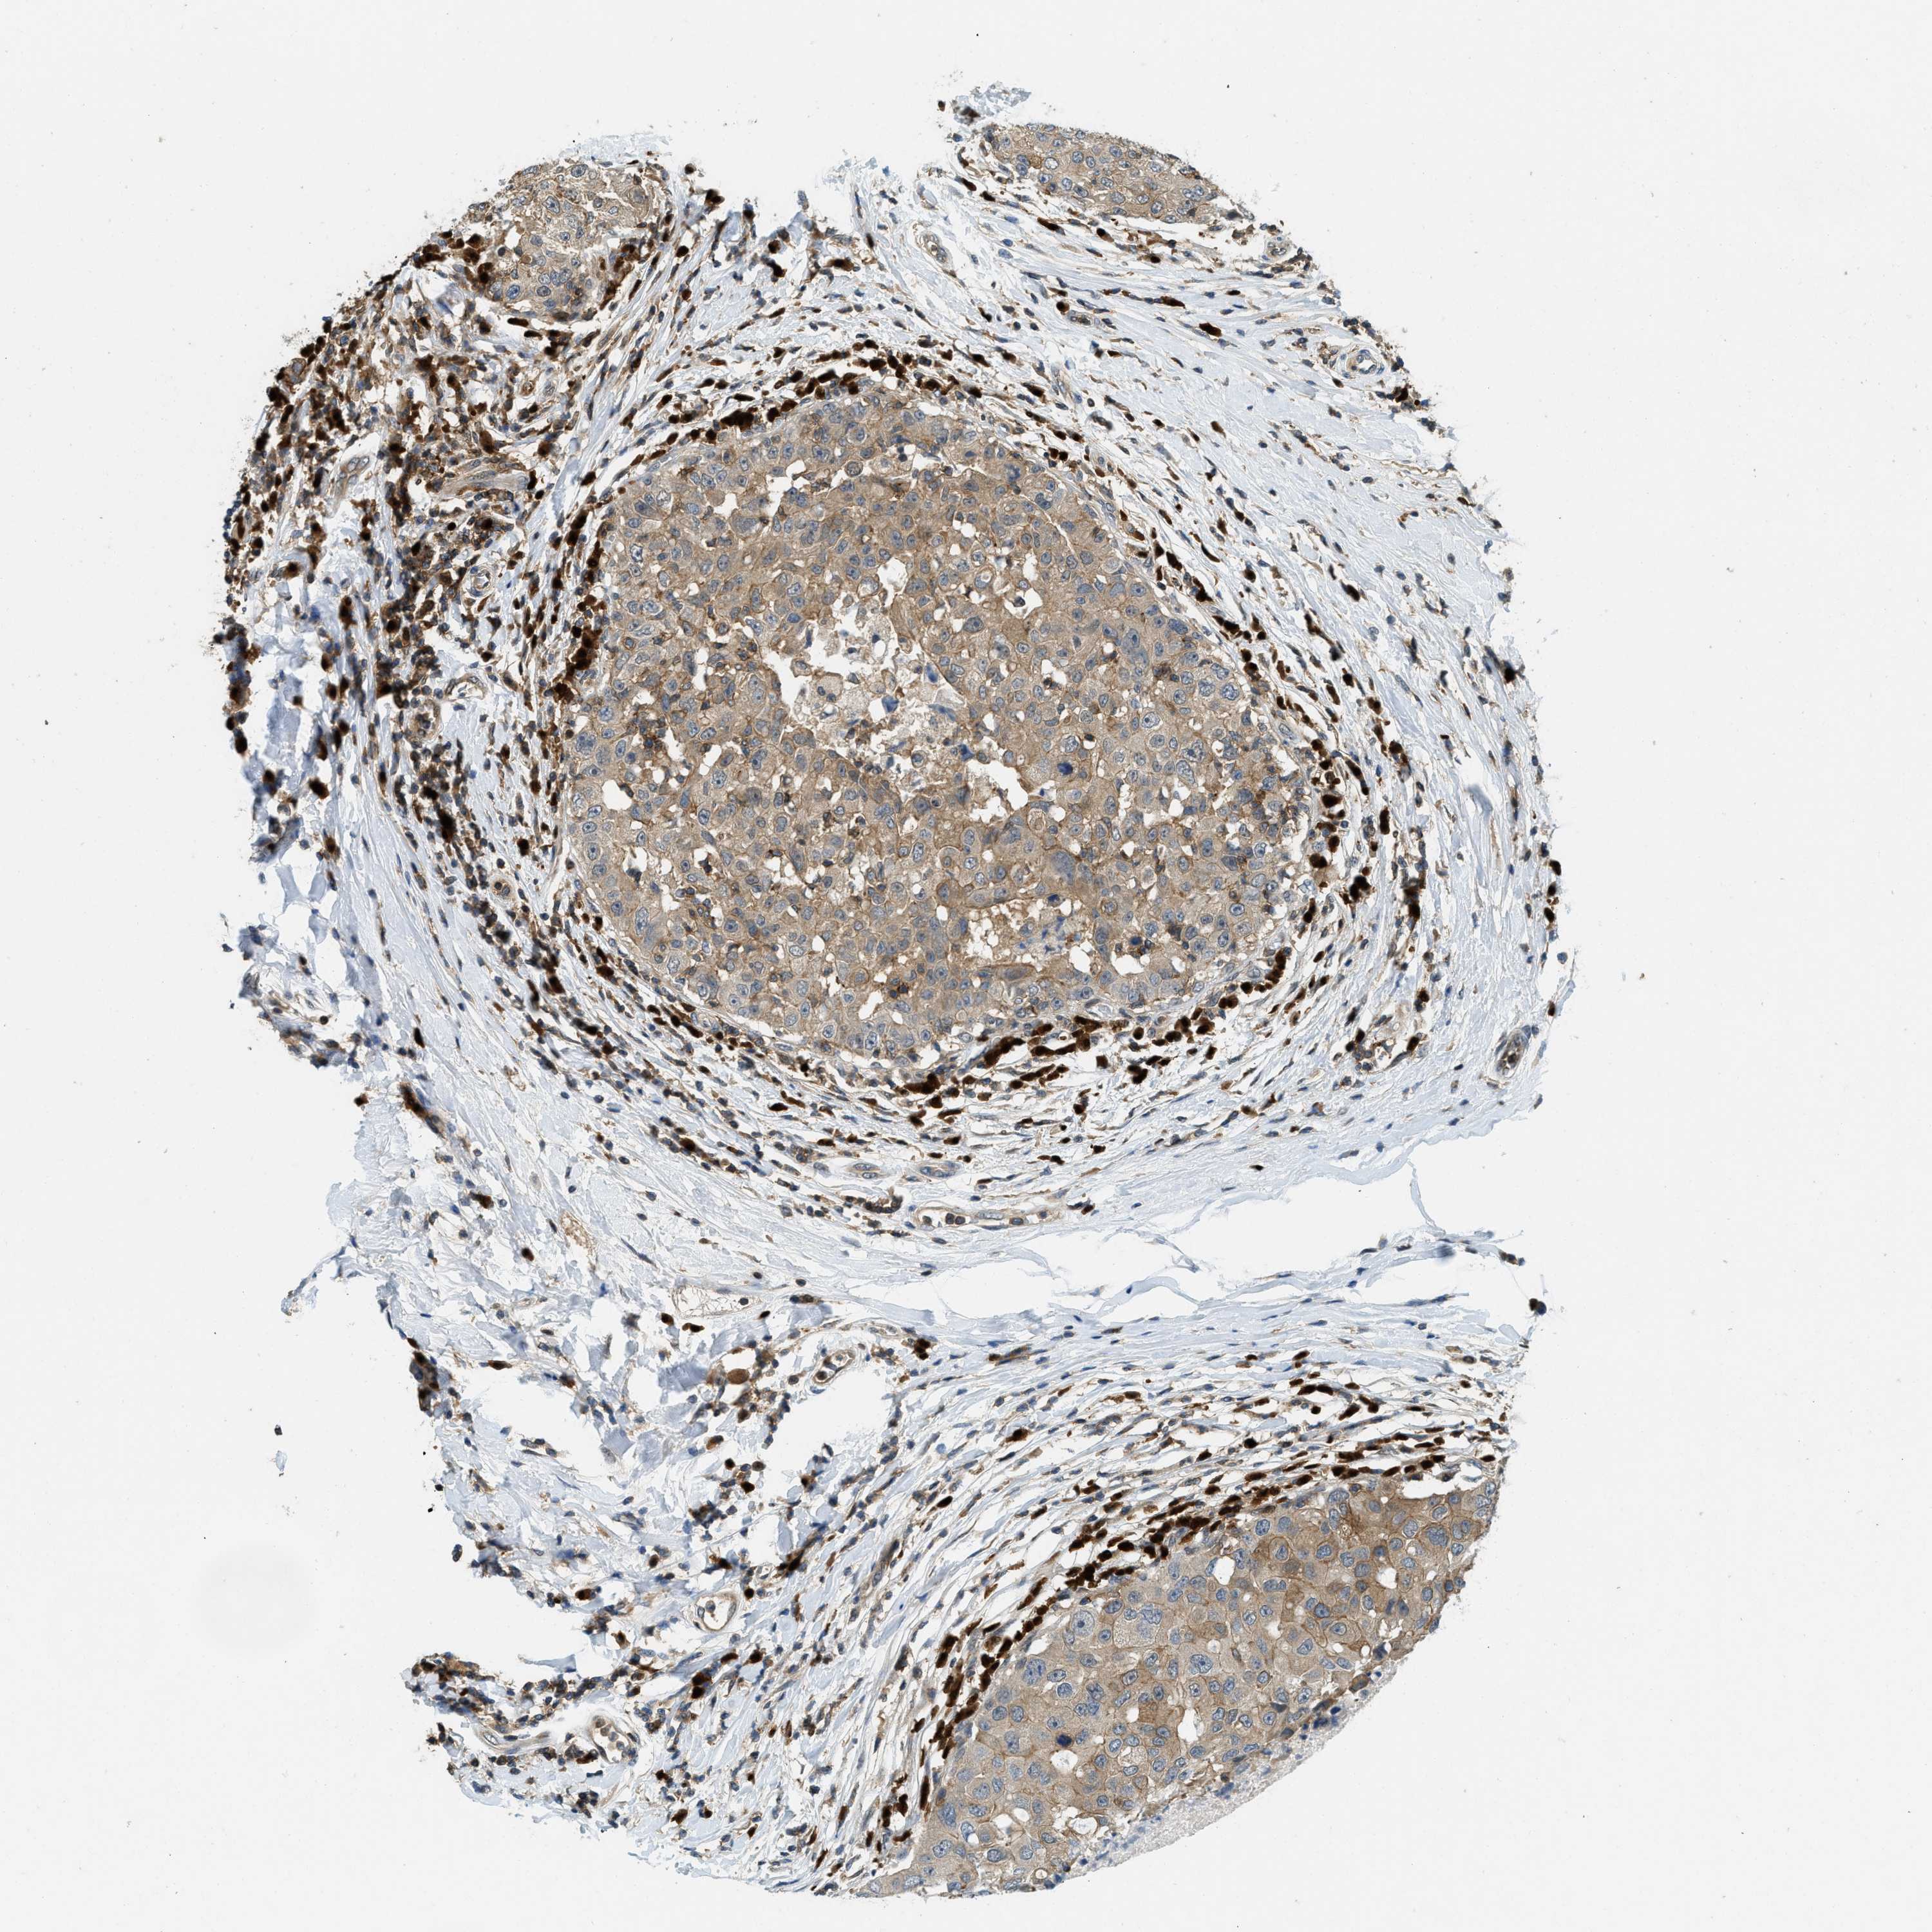

CANCER BREAST CANCER Show tissue menu

BRCA TCGA BRCA VALIDATION PROTEIN EXPRESSION